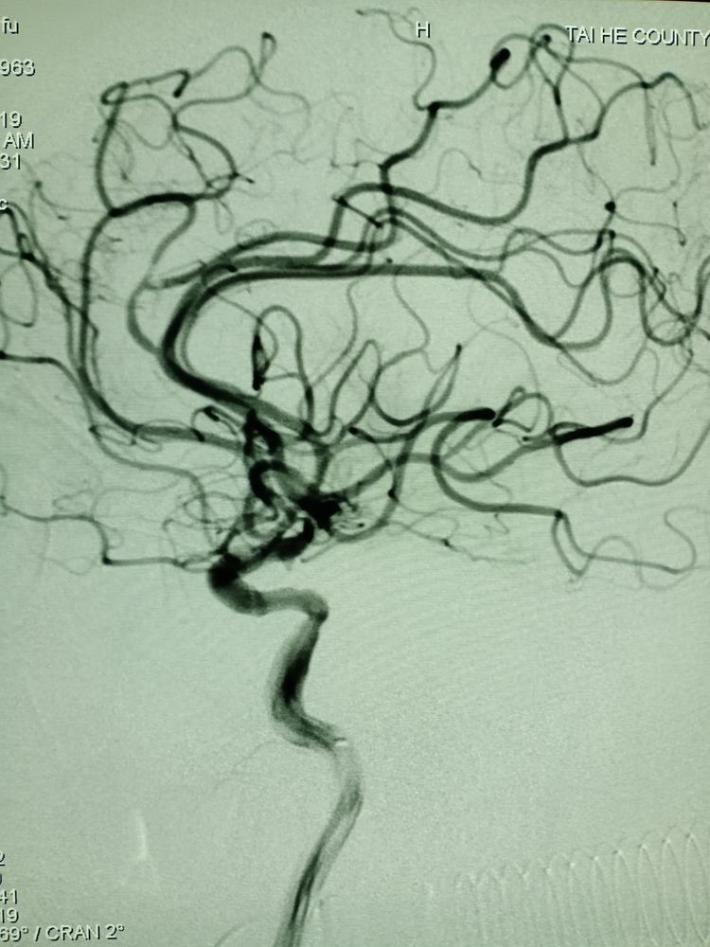

左侧椎动脉造影提示:右侧后交通动脉开放,后循环向前循环代偿供血。

微导管超选至闭塞血管的远端,手推造影证实在真腔。

国产取栓支架尼科4mm*20mm成功打开,前向血流恢复。